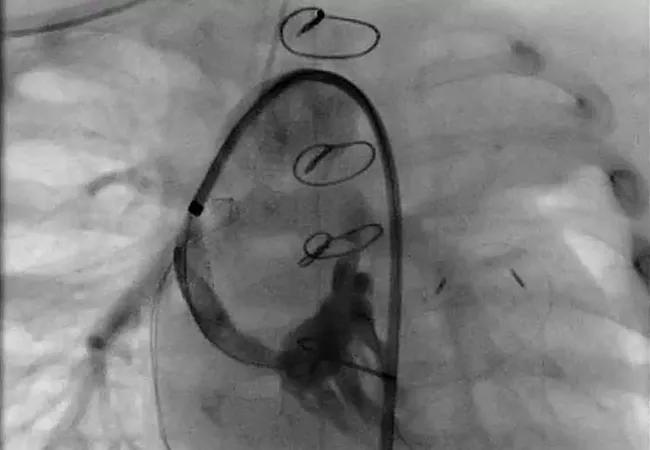

Featured image: Right ventricular angiogram documenting extensive right ventricular-dependent coronary circulation.

Image reprinted with permission under the Creative Commons CC-BY-NC-ND license. It originally appeared in the following: Najm HK, Costello JP, Karamlou T, Amdani S, Suntharos P, Marino B. Revascularization of coronary circulation in pulmonary atresia with intact ventricular septum and right ventricular-dependent coronary circulation. J Thorac Cardiovasc Surg. 2023 May 6:S0022-5223(23)00330-6. doi: 10.1016/j.jtcvs.2023.04.007.